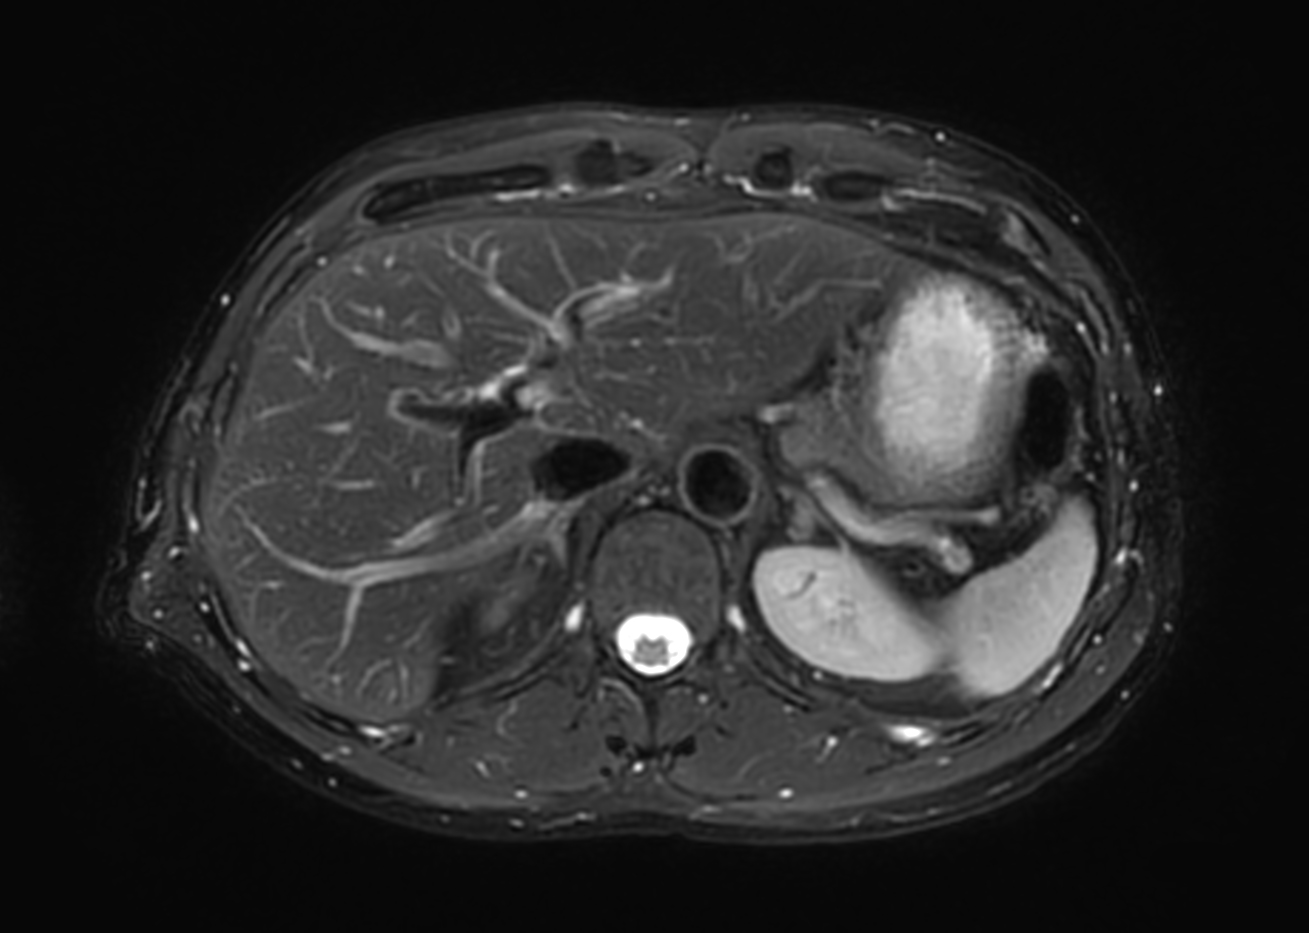

Helium-free MR operations:

Liver on BlueSeal magnet

Spital Uster, Switzerland

• Coil

• Clinical Application